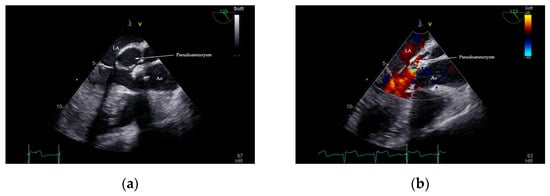

Native Aortic Valve Endocarditis Complicated by Splenic Infarction and Giant Mitral-Aortic Intervalvular Fibrosa Pseudoaneurysm—A Case Report and Brief Review of the Literature

2. Case Presentation